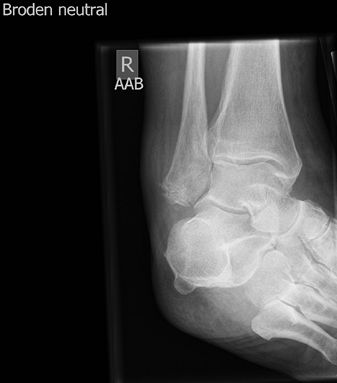

Posterior Subtalar Joint

The Broden view is a useful adjunct view to look at the

posterior subtalar joint to assess for intraarticular fractures and

arthritis.

Figure 24 Broden view of posterior subtalar joint.